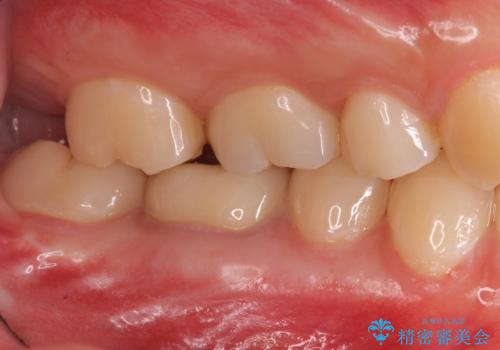

樹脂をセラミックにしたい ジルコニアクラウンでの治療

- 樹脂をやり替えたいとのことで来院されました。

特に大きな虫歯もありませんでしたが、残った歯が薄かったためクラウンでの修復処置を行いました。

インレーにすると残った歯が薄くなってしまう場合は術後の破折リスクが高いためクラウンで修復することがあります。